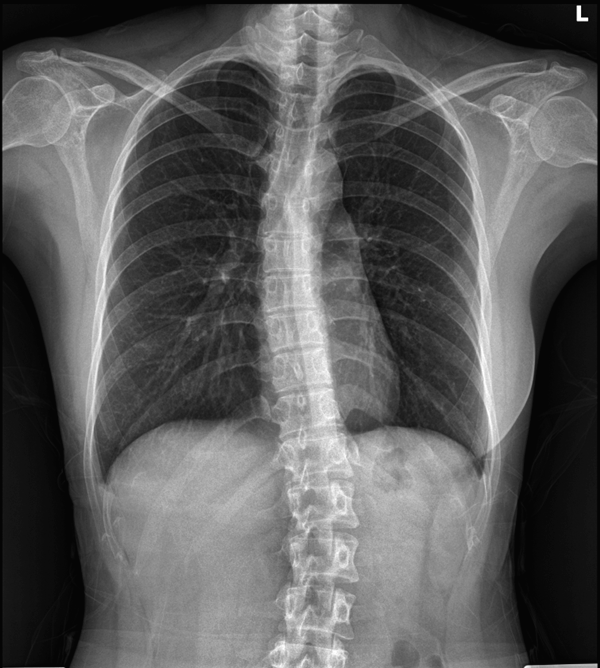

X-ray (엑스레이)

척추 구조와 간격 확인

퇴행성 변화나 측만증 진단 가능

다만, 디스크나 근육은 보이지 않아요